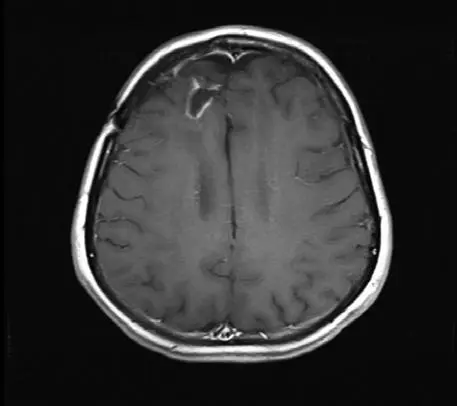

Исследования с вирусом полиомиелита на данный момент ведутся в основном на пациентах с продвинутой стадией глиобластомы – одного из самых смертоносных и агрессивных видов рака мозга, который часто убивает через несколько недель после того, как все стандартные способы лечения перестают работать. Ученым удалось продлить жизнь нескольких пациентов на месяцы и даже годы [9].

Энцефалограммы 20-летнего студента, которого лечат модифицированным вирусом полиомиелита (PVS-RIPO), вводимым через катетер, подсоединенный прямо к опухоли.